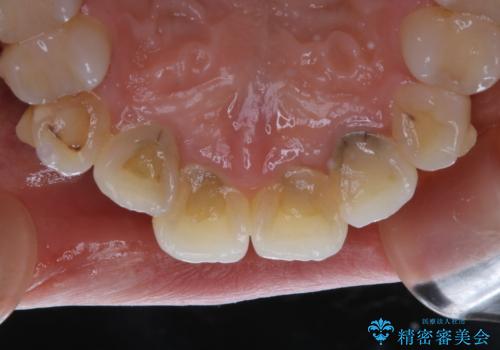

インビザライン矯正治療中のPMTC

- インビザライン中にクリーニングを希望とのことでした。PMTC30分コースを行いました。

矯正治療中は虫歯や歯周病リスクが高くなります。

インビザライン矯正治療はマウスピースを長時間使用するため、歯石や汚れなどが付着したままだと、フィットが悪くなったり、口臭が強く出たりする原因につながることもあります。

定期的にPMTCを行うことをおすすめします。